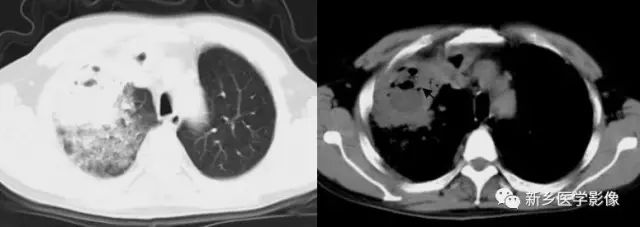

⑦.胸膜凹陷征

表现为肿块与邻近胸壁间的三角形或喇叭口状影,其尖端指向或深入病灶内。为病变瘢痕收缩牵拉邻近胸膜所致,肿瘤及炎性病变皆可出现此征象。

胸部CT图:a. 胸部CT肺窗和b. 纵隔窗显示胸膜凹陷征(↑)